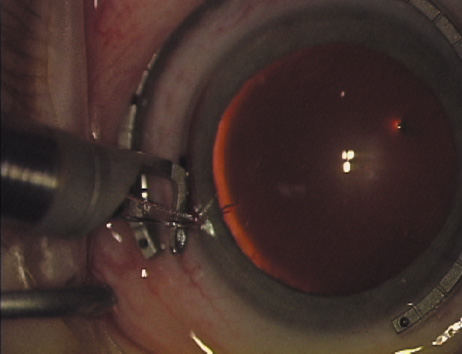

Fig. 11. Opposite relaxing incision is completed. (Reprinted from Hardten DR, Lindstrom RL, Davis EA. Phakic Intraocular Lenses: Principles and Practice. Thorofare, NJ: SLACK Incorporated, 2004, with permission.)

Case 2 is a 79-year-old woman who presented with a very dense left cataract. Her refraction was recorded at −2.25 +2.75 × 125 with a difficult end point. Her manual keratometry and topography measurements were consistent and revealed slightly less than 1.75 D at 120 degrees. Because of the questionable refraction, greater value was placed on the corneal measurements. Based upon the cataract nomogram, the plan was for paired LRIs of 40 degrees to be placed over the steep 120-degree axis (Figs. 1219).

Fig. 19. The temporal single-plane clear corneal incision is placed independent of the LRIs. (Reprinted from Hardten DR, Lindstrom RL, Davis EA. Phakic Intraocular Lenses: Principles and Practice. Thorofare, NJ: SLACK Incorporated, 2004, with permission.)

Case 3 is a 48-year-old bilateral hyperope who presented for a refractive surgical consultation. The refraction in his left eye was found to be +3.25 +1.75 × 85. Keratometry was somewhat flat but confirmed WTR cylinder as did corneal topography. Based upon the patient's age, refraction, and somewhat shallow anterior chambers, the decision was made to proceed with a refractive lens exchange. The NAPA nomogram called for LRIs of 55 to 60 degrees with intraoperative pachymetry. Intraoperative keratoscopy confirmed the steep 85-degree meridian (Figs. 2029).

Fig. 28. 6A side-port incision is created for the surgeon's non-dominant right hand, taking care not to intersect the LRI.

Fig. 29. The single-plane RLE incision is completed.